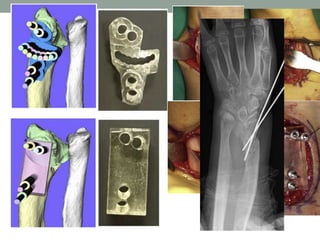

Nuestro proyecto . . .

• Pacientes con deformidad de Madelung

• Físis cerrada

• TAC

• Planificación preoperatoria

• Guías personalizadas para osteotomía

Necesitamos la impresora nosotros?

• Impresoras 3D

• Protaico  PYME

100% Chilena

• Maxilofacial CLC

• Experiencia en IT

• Error de 0,01mm

• Costo de la impresión

• +- 80.000 pesos

Ejemplo . . .